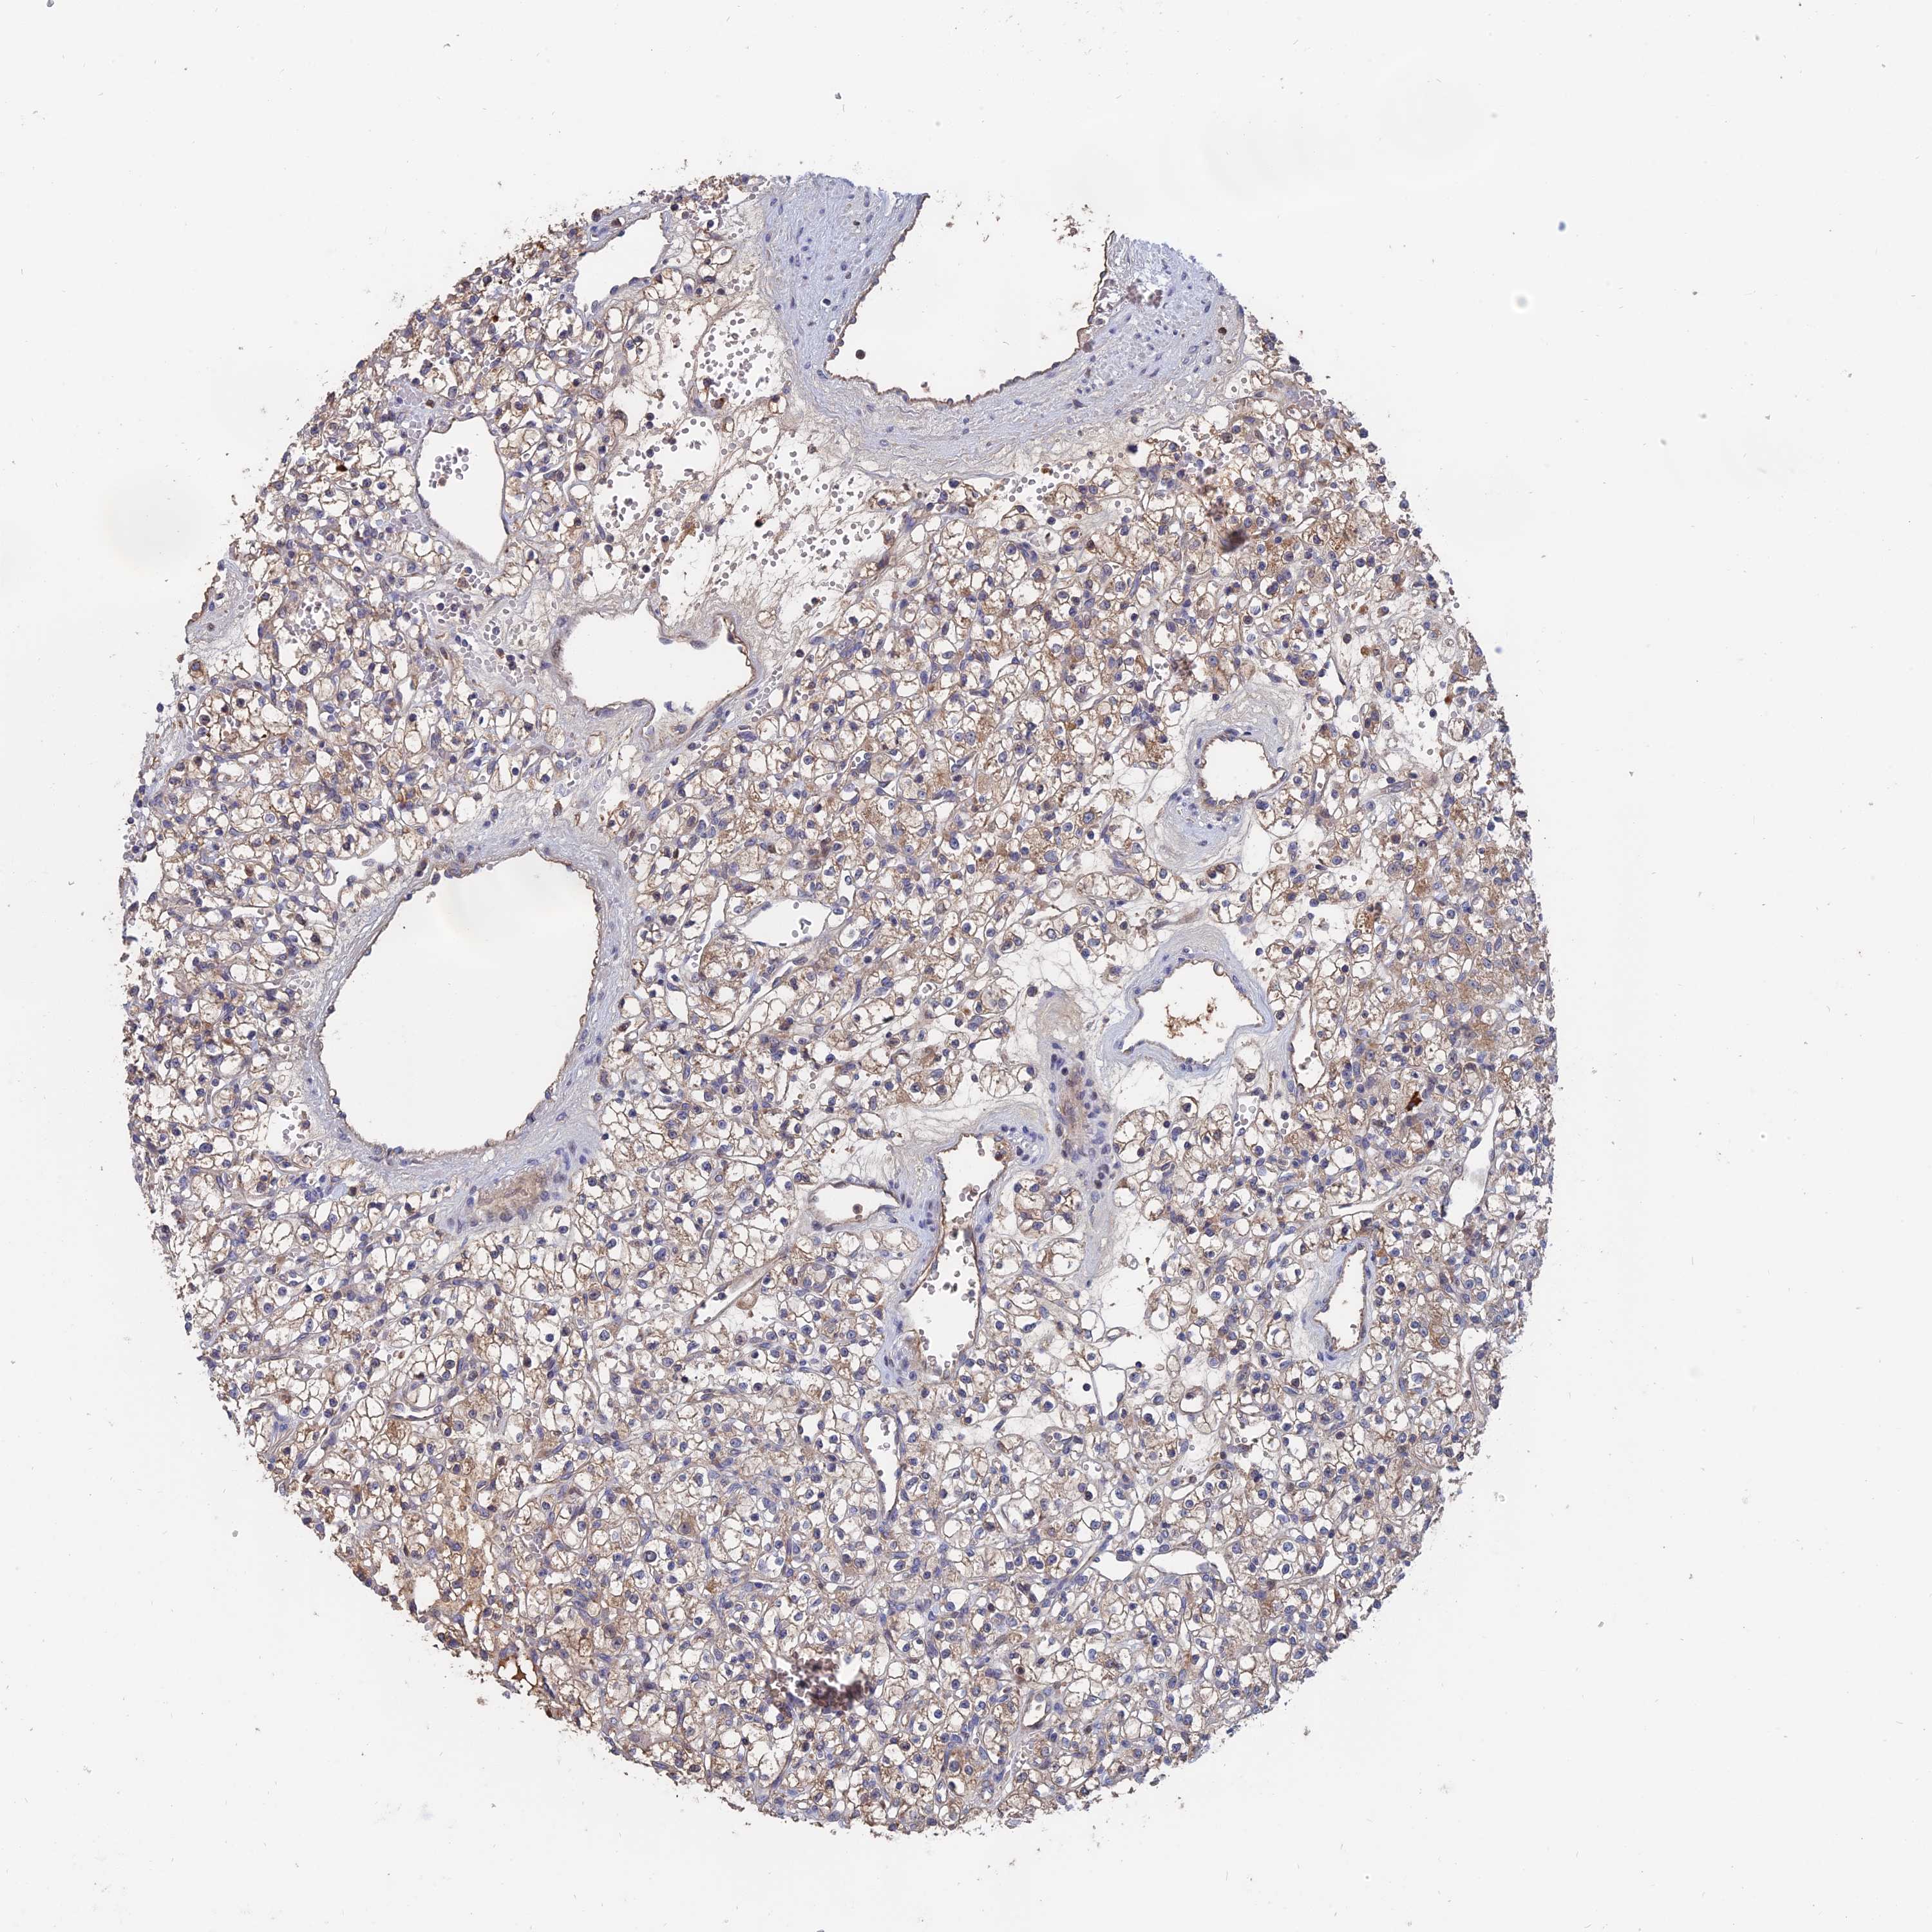

KIDNEY RENAL CLEAR CELL CARCINOMA (VALIDATION) - Interactive survival scatter ploti

The Survival Scatter plot shows the clinical status (i.e. dead or alive) for all individuals in the patient cohort, based on the same data that underlies the corresponding Kaplan-Meier plots. Patients that are alive at last time for follow-up are shown in blue and patients who have died during the study are shown in red.

The x-axis shows the expression levels (FPKM) of the investigated gene in the tumor tissue at the time of diagnosis. The y-axis shows the follow-up time after diagnosis (years). Both axes are complimented with kernel density curves demonstrating the data density over the axes. The top density plot shows the expression levels (FPKM) distribution among dead (red) and alive patients (blue). The right density plot shows the data density of the survived years of dead patients with high and low expression levels respectively, stratified using the cutoff indicated by the vertical dashed line through the Survival Scatter plot. This cutoff is automatically defined based on the FPKM cutoff that minimizes the p-score. The cutoff can be changed by dragging the vertical line or by entering a cutoff value in the square labeled "Current cut-off".

Under the Survival Scatter plot the p-score landscape (black curve; left axis) is shown together with dead median separation (red curve; right axis). Dead median separation is the difference in median mRNA expression between patients who have died with high and low expression, respectively. It is calculated as follows: median FPKM expression of dead patients with high expression - median FPKM expression of dead patients with low expression. This is intended to aid the user in visually exploring custom cutoffs and the associated p-scores and dead median separation.

Individual patient data is displayed and can be filtered by clicking on one or more of the category buttons on the top of the page. Categories describing expression level and patient information include: high, low, alive, dead, female, male and tumor stages. The scale of the x-axis can be toggled between linear and log-scale by clicking on the "x log" button. Mouse-over function shows TCGA ID, patient information and mRNA expression (FPKM) for each patient.

& Survival analysisi

Kaplan-Meier plots summarize results from analysis of correlation between mRNA expression level and patient survival. Patients were divided based on level of expression into one of the two groups "low" (under cut off) or "high" (over cut off). X-axis shows time for survival (years) and y-axis shows the probability of survival, where 1.0 corresponds to 100 percent.

SLC33A1 is not prognostic in Kidney Renal Clear Cell Carcinoma (validation)

: 17.47

Average pTPM 17.3

Number of samples 100